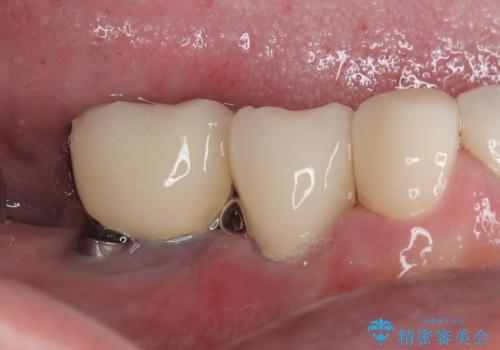

インプラント埋入時に植立具合の安定性を測定したところ、十分な数値が得られたため、速やかに仮歯を装着して咬合回復をさせることができました。

抜歯を含めた外科処置を1回に抑えることができ、あっという間に治療を終えることができました。